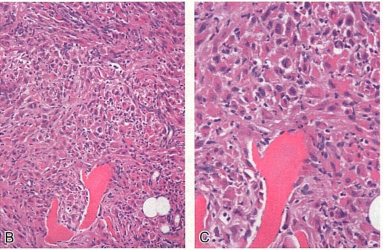

患者男,16岁。右踝关节疼痛不适。影像学检查显示右胫骨下端和足骨多灶性病变,临床和影像学诊断多骨性朗格汉斯细胞组织细胞增生症,行活检,镜下形态如图所示。